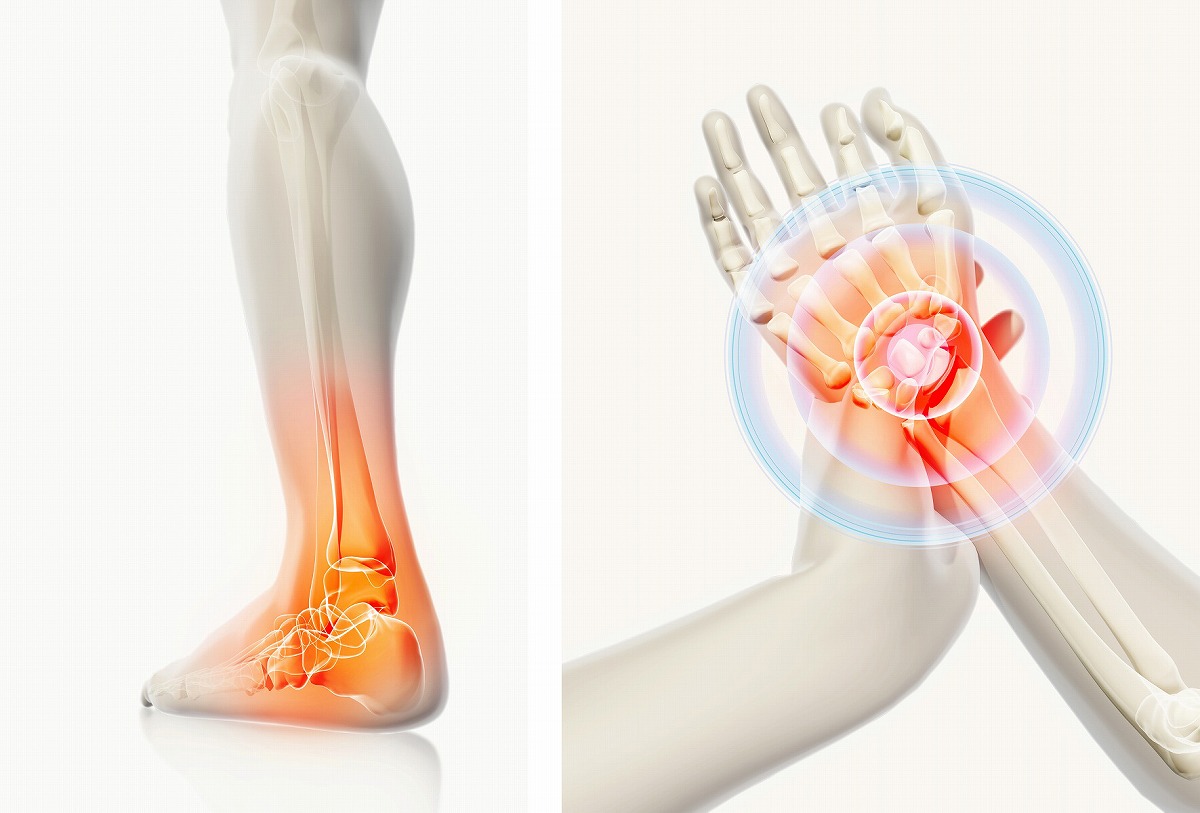

手足のしびれ・しびれる

手足のしびれは、ねんざが代表的ですが、痛めたあとに適切な治療を受けず、クセになったり痛みが慢性化することが多いです。足首の痛みの症状、原因、診断方法、そして治療について詳しく説明します。

手足のしびれは、ねんざが代表的ですが、痛めたあとに適切な治療を受けず、クセになったり痛みが慢性化することが多いです。足首の痛みの症状、原因、診断方法、そして治療について詳しく説明します。